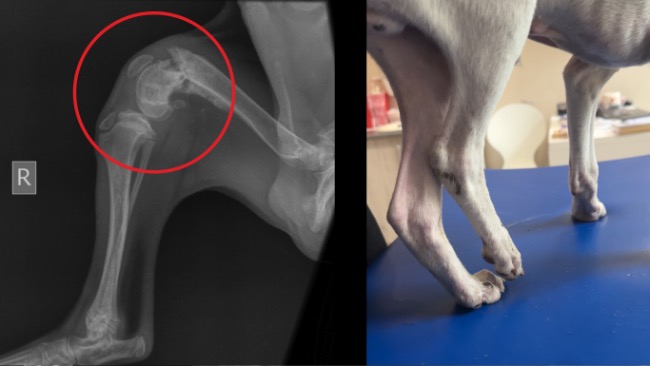

Kiedy Tango trafił pod naszą opiekę, okazało się, że jego stan jest dramatyczny. Jest skrajnie wychudzony, jego drobne ciało było całe pokryte pchłami i kleszczami. Kuleje na tylną łapę i nie jest w stanie jej postawić. Od razu trafił do kliniki weterynaryjnej, gdzie wykonano badania krwi oraz zdjęcia RTG.

Diagnoza potwierdziła nasze obawy – Tango ma złamanie poprzeczne w dalszej części kości udowej, które zaczęło się już zrastać w nieprawidłowy sposób. Dodatkowo uszkodzone są więzadła, być może całkowicie zerwane. Wszystko wskazuje na to, że został potrącony przez samochód i przez długi czas żył z ogromnym bólem, pozostawiony sam sobie.

Weterynarze podjęli decyzję o konieczności ponownego złamania i prawidłowego złożenia kości. To bardzo skomplikowany zabieg ortopedyczny, który musi wykonać specjalista. Bez niego łapa nigdy nie będzie sprawna, a Tango już zawsze będzie cierpiał.